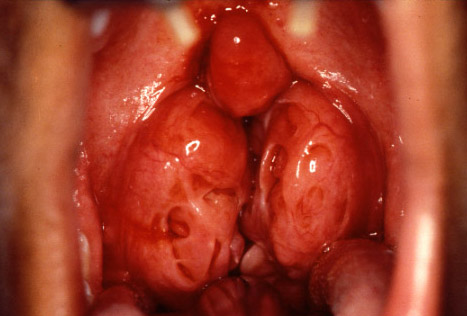

Hypertrophic tonsils (4+ size).